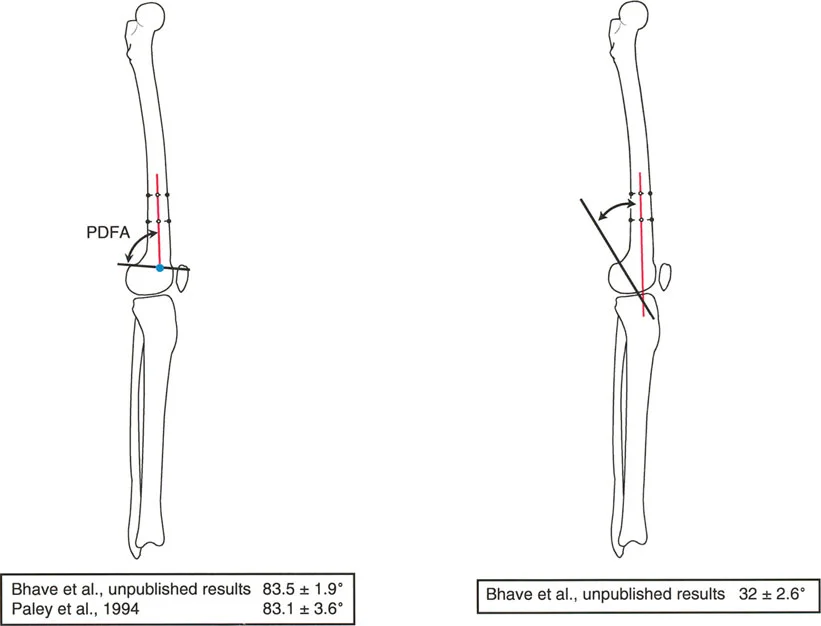

الزاوية الفخذية البعيدة الخلفية (PDFA) وخط بلومنسات (Blumensaat's Line)

توجيه الجزء السفلي من عظم الفخذ في المستوى السهمي أقل شيوعاً في النقاش، ولكنه مهم أيضاً لعمليات قطع العظم في هذه المنطقة.

* PDFA: الزاوية الفخذية البعيدة الخلفية الطبيعية هي 83.1 درجة ± 3.6 درجة.

* زاوية خط بلومنسات: هي الزاوية المتكونة بين المحور التشريحي لعظم الفخذ وخط بلومنسات (سقف الشق بين اللقمتين)، وتقاس بحوالي 32 درجة ± 2.6 درجة.